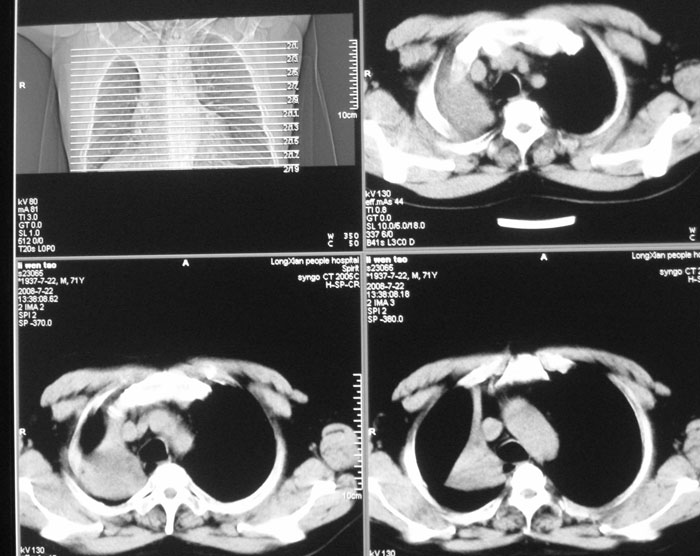

以下是引用zhangjixiang在2008-8-6 20:02:00的发言:[br]右主支气管明显变窄伴右上叶尖段不张,结合年龄,考虑右侧中央型肺癌可能性大,纤支镜检可确诊.